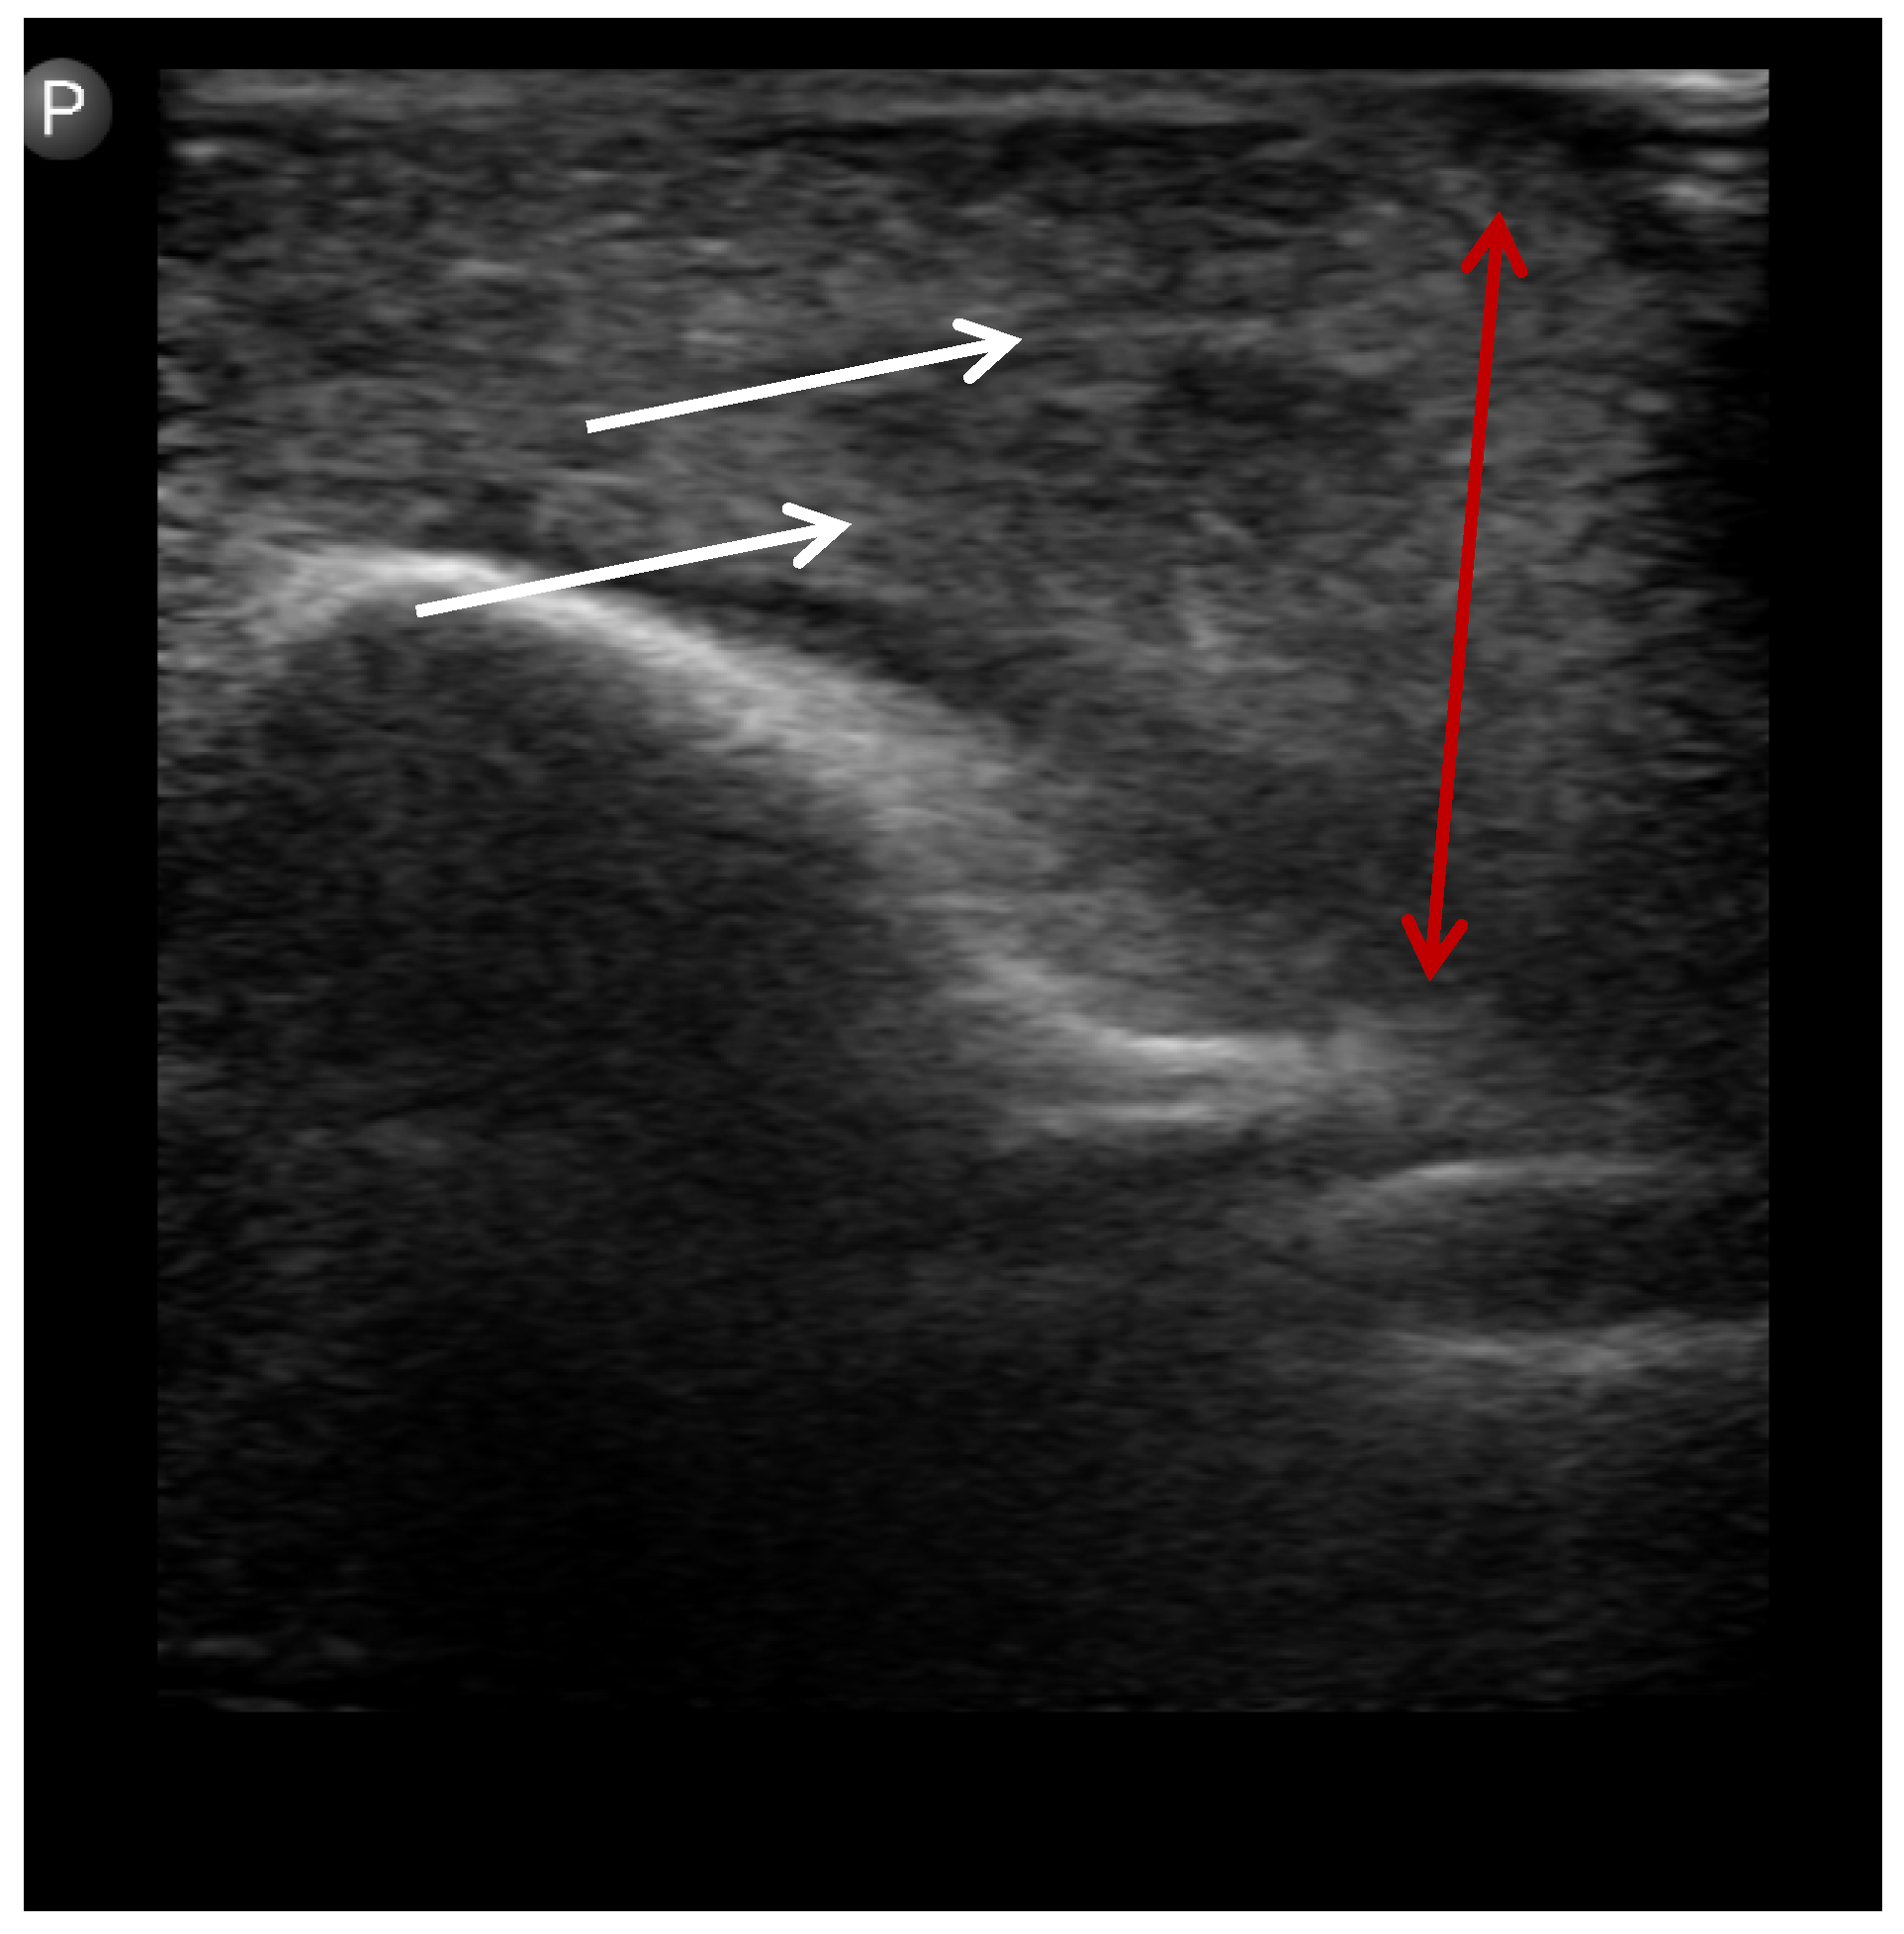

Figure 3. Ultrasound image showing cellulitis. White arrows: diffuse fascial thickening without a discrete collection. Red arrow: infiltration consistent with cellulitis.